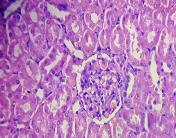

All the animals were observed daily for clinical signs of toxicity and morbidity. Individual animal body weights were recorded at receipt (on day 1) and weekly thereafter and at the time of sacrifice (fasting body weights). Histological examinations of various organs (brain, kidney, liver, small intestine and stomach) were carried out after 28 d using haematoxylin and eosin as staining agents. The organs were preserved in 10 % formalin solution.

On administration of TPSY, the animals in all groups were found to survive at the end of 28 d of study. The histological results are shown in table 4. Liver tissue showed minimal degeneration of hepatocytes compared to control at the highest dose of 350 mg which was however reported to be non-toxic.

Mild tubular degeneration was observed in kidneys Stomach tissue displayed moderate changes compared to control, with minimal degeneration of mucosal cellsat highest dose of 350 mg. Large intestine showed marked submucosal edema but the mucosal tissue appeared to be normal at the highest dose of 350 mg. No abnormality was observed in brain tissues at a low and medium dose. Mild submucosal edema was observed at 350 mg/kg. These results point to the negligible toxicity associated with the thiolated polymer and hence it can be considered to be safe for use as a pharmaceutical excipient.

Table 4: Histological results of repeated dose toxicity studies of TPSY (n=5)

| Organs | Normal saline | TPSY dose strength | ||

| Control | 70 mg/kg | 175 mg/kg | 350 mg/kg | |

| Liver | Normal architecture of liver, nothing abnormal detected. | Nothing abnormal detected. | Minimal degeneration of hepatocytes. | Minimal degeneration of hepatocyte and infiltration of inflammatory cells. |

| Kidney | Normal architecture of kidney, nothing abnormal detected. | Minimal tubular degeneration. | Mild tubular degeneration and congestion of blood vessels. | Mild tubular degeneration. |

| Stomach | Normal architecture of Stomach, Nothing abnormal detected. | Minimal degeneration of mucosal lining cells. | Mucosal cells were enlarged and were darkly stained. | Minimal degeneration of mucosal cells, accumulation of dark staining material in the gland. |

| Brain | Normal architecture of the brain, Nothing abnormal detected. | Nothing abnormal detected. | Nothing abnormal detected. | Minimal neuronal degeneration. |

| Large intestine | Papillary projections with goblet cells. | Mucosal lining no infiltration of inflammatory cells. | Minimal infiltration of inflammatory cells and congestion. | Marked submucosal edema, mucosal tissue appears normal. |

Fig. 8: Histology of various tissues at highest dose strength of 350 mg/kg body weight